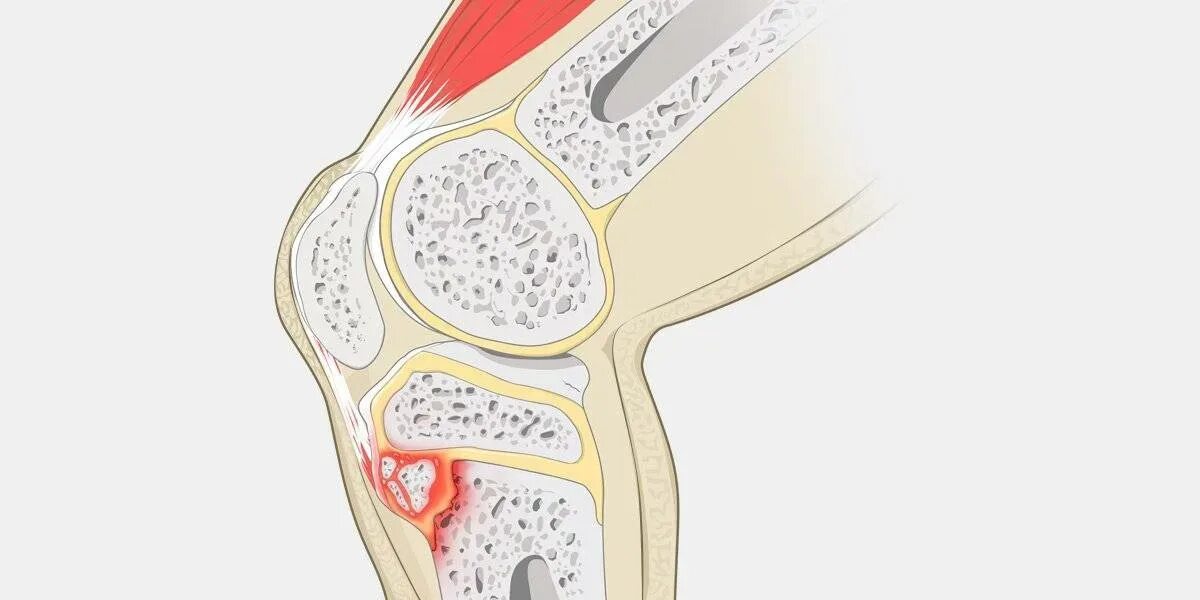

Болезнь осгут шляттера